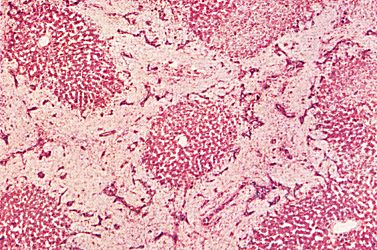

The histology of the liver is usually described on the basis of smaller units, called liver lobules. The most common description is that of the classic liver lobule, which consists of a number of liver cells (hepatocytes) surrounded by connective tissue. Such a liver lobule is usually hexagonal, with a central vein in the middle. The liver cells are arranged in plates with blood filled spaces, the sinusoids, in between the various plates of cells. At many of the corners of these hexagonal lobules, triads are found. Each consist of a bile duct, vein (branch of portal vein), and artery (branch of hepatic artery).

The following slide is of a cross section of the liver. Pig liver has more pronounced connective tissue septae and is used here to demonstrate the septae.